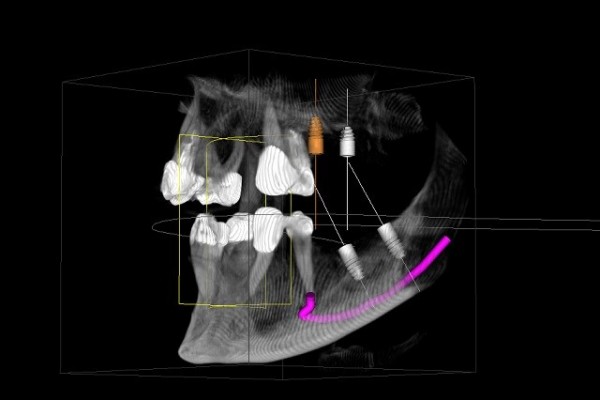

Mit der Digitalen Volumentomographie (DVT) bieten wir unseren Patienten ein hochmodernes dreidimensionales Diagnoseverfahren, welches eine deutlich besseren Bildqualität, erhöhte Sicherheit für Patient und Behandler sowie eine geringere Strahlendosis als bei einer herkömmlichen CT bedeutet .

Die DVT arbeitet mit Röntgenstrahlen. Wie auch die Computertomographie (CT) können mit der DVT hochauflösende Schnittbilder erstellt werden, diese haben jedoch eine deutlich bessere Auflösung. Hierdurch ist eine noch genauere Diagnose und spätere Therapie möglich.

Die Röntgenröhre produziert zweidimensionale Einzelaufnahmen, die von einem Hochleistungsrechner zu einem dreidimensionalen Datensatz umgerechnet werden.

Innerhalb kürzester Zeit wird so direkt eine präzise Diagnosegrundlage erstellt, der wir alle Informationen entnehmen können, die wir für Ihre Therapieplanung benötigen.

• Lagebeurteilung von Weisheitszähnen und deren Bezug zum Gesichtsnerv und der Kieferhöhle

• Implantatplanung in der 3D Simulation

• exakte Positionierung von Implantaten

• Einschätzung des Knochenangebots und der Knochenbeschaffenheit vor der Implantatversorgung